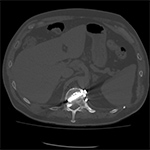

|

| 70 year-old man with history of L1 and L3 injury and T11-L3 spinal fusion in the 1990's. Recent worsening of chronic lower back pain. Standard radiographs (left two images) show a vertebral body corpectomy cage at T12-L3 with placement of a left lateral side plate at the same levels. There are two proximal screws at T12, one of which enters the spinal canal as shown on subsequent CT (right two images). There are two distal screws at L3, the most distal of which enters the L3-4 disk space (lateral radiograph). |